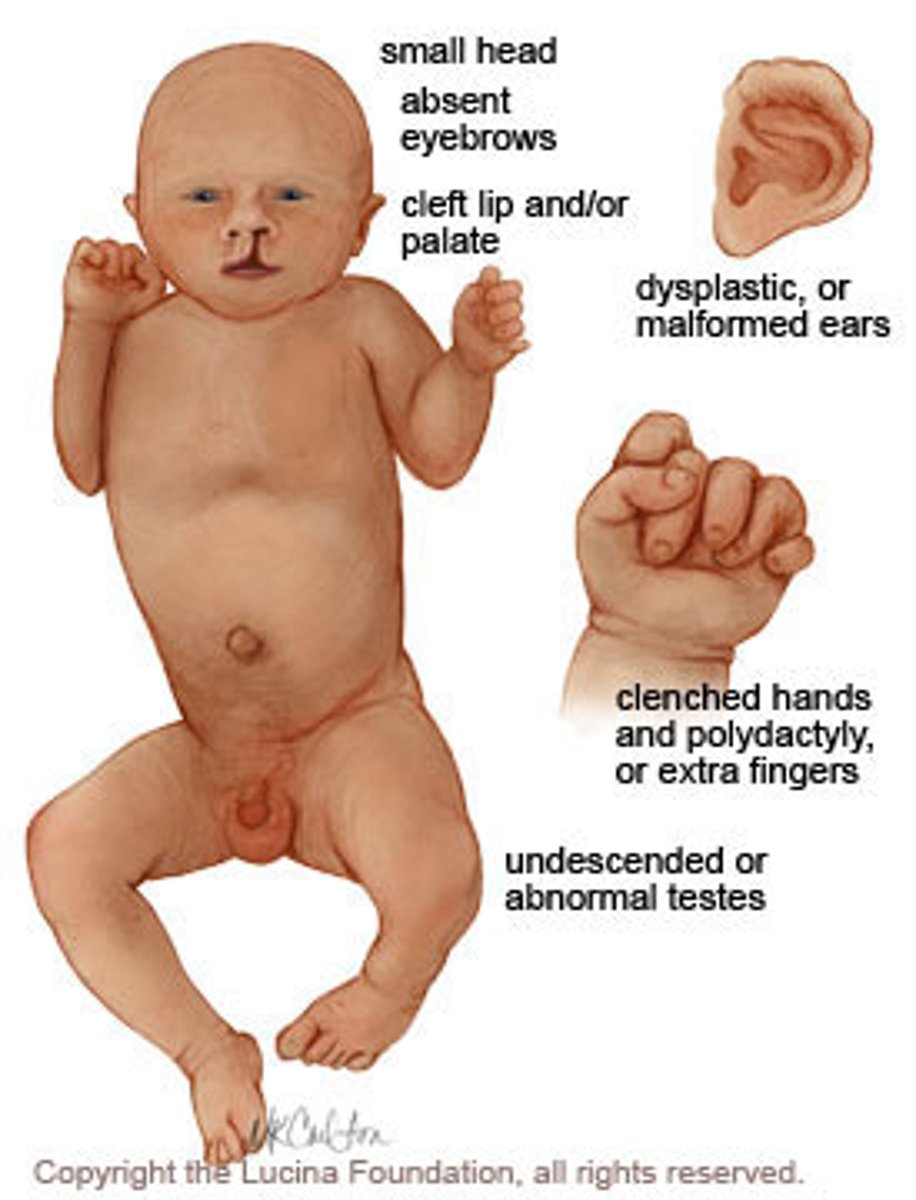

Which trisomy is associated with holoprosencephaly?

trisomy 13 (Patau's)